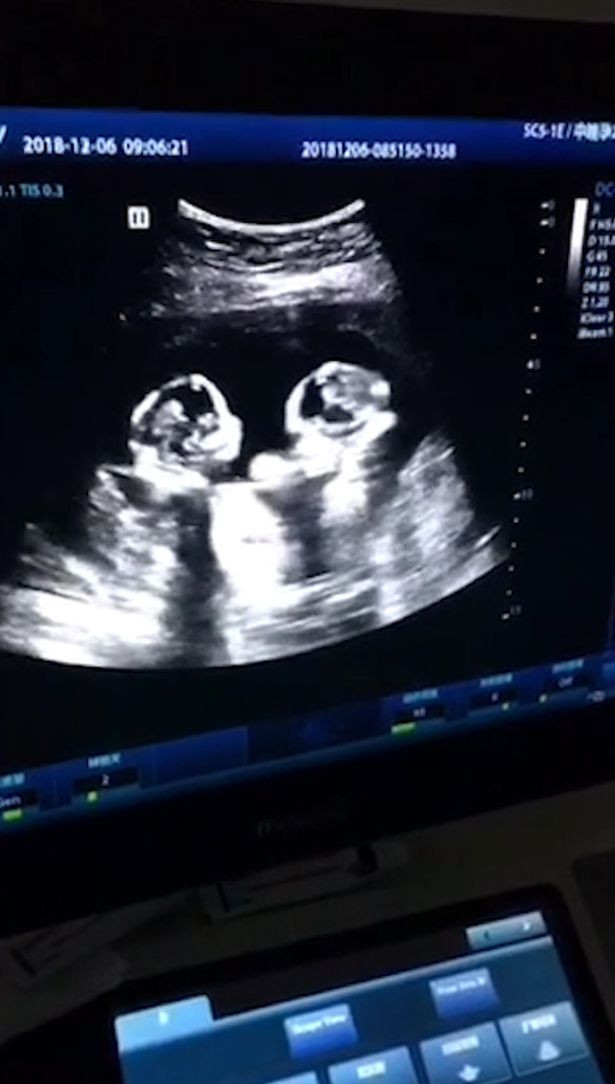

Những hình ảnh và clip siêu âm được một y tá ở bnh viện phụ sản thành phố Ngân Xuyên (Trung Quốc) ghi lại từ tháng 12 năm ngoái cho thấy, 2 bé gái song sinh nằm đối diện nhau và có vẻ như bất ngờ đánh nhau trong bụng mẹ.

| Hình ảnh siêu âm của cặp song sinh. |

| Khoảnh khắc được cho là đánh nhau của cặp song sinh. |

Theo Giám đốc trung tâm tiền sản ở Ngân Xuyên, hành động của cặp song sinh có thể gây nguy hiểm vì có vẻ như 2 bé đã phát triển trong cùng 1 “phòng”, trong khi theo lẽ thường, các cặp song sinh phát triển trong 2 “phòng”.

Được biết, trong 30 triệu trường hợp, chỉ có 1 trường hợp hiếm gặp như vậy xảy ra.